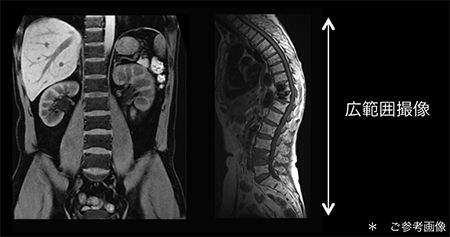

ワイドカバレッジ(Large FOV)

高画質を支える最も重要なハードウェアはマグネットです。SIGNA Voyagerは高精細シムチップにより,より極め細やかな磁場調整が可能になりました。その結果ワイドボア1.5Tの中でクラス最高レベルの0.33ppm(40cmDSV, Typical値)*1の静磁場均一性を有することで局所から広範囲まで高画質を実現します。広範囲の撮像を一度に可能にし,患者さんに効率の良い検査を提供します。